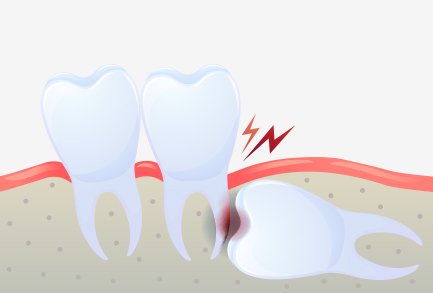

사랑니 충치

비정상적인 위치에 매복되어 자란 사랑니는

염증과 통증을 일으킬 수도 있으므로

발치하는 것이 좋습니다.

누워서 자란 사랑니의 경우

바로 앞의 어금니 뿌리를 압박해 염증을 일으키거나

턱뼈의 신경까지 손상시킬 수 있습니다.